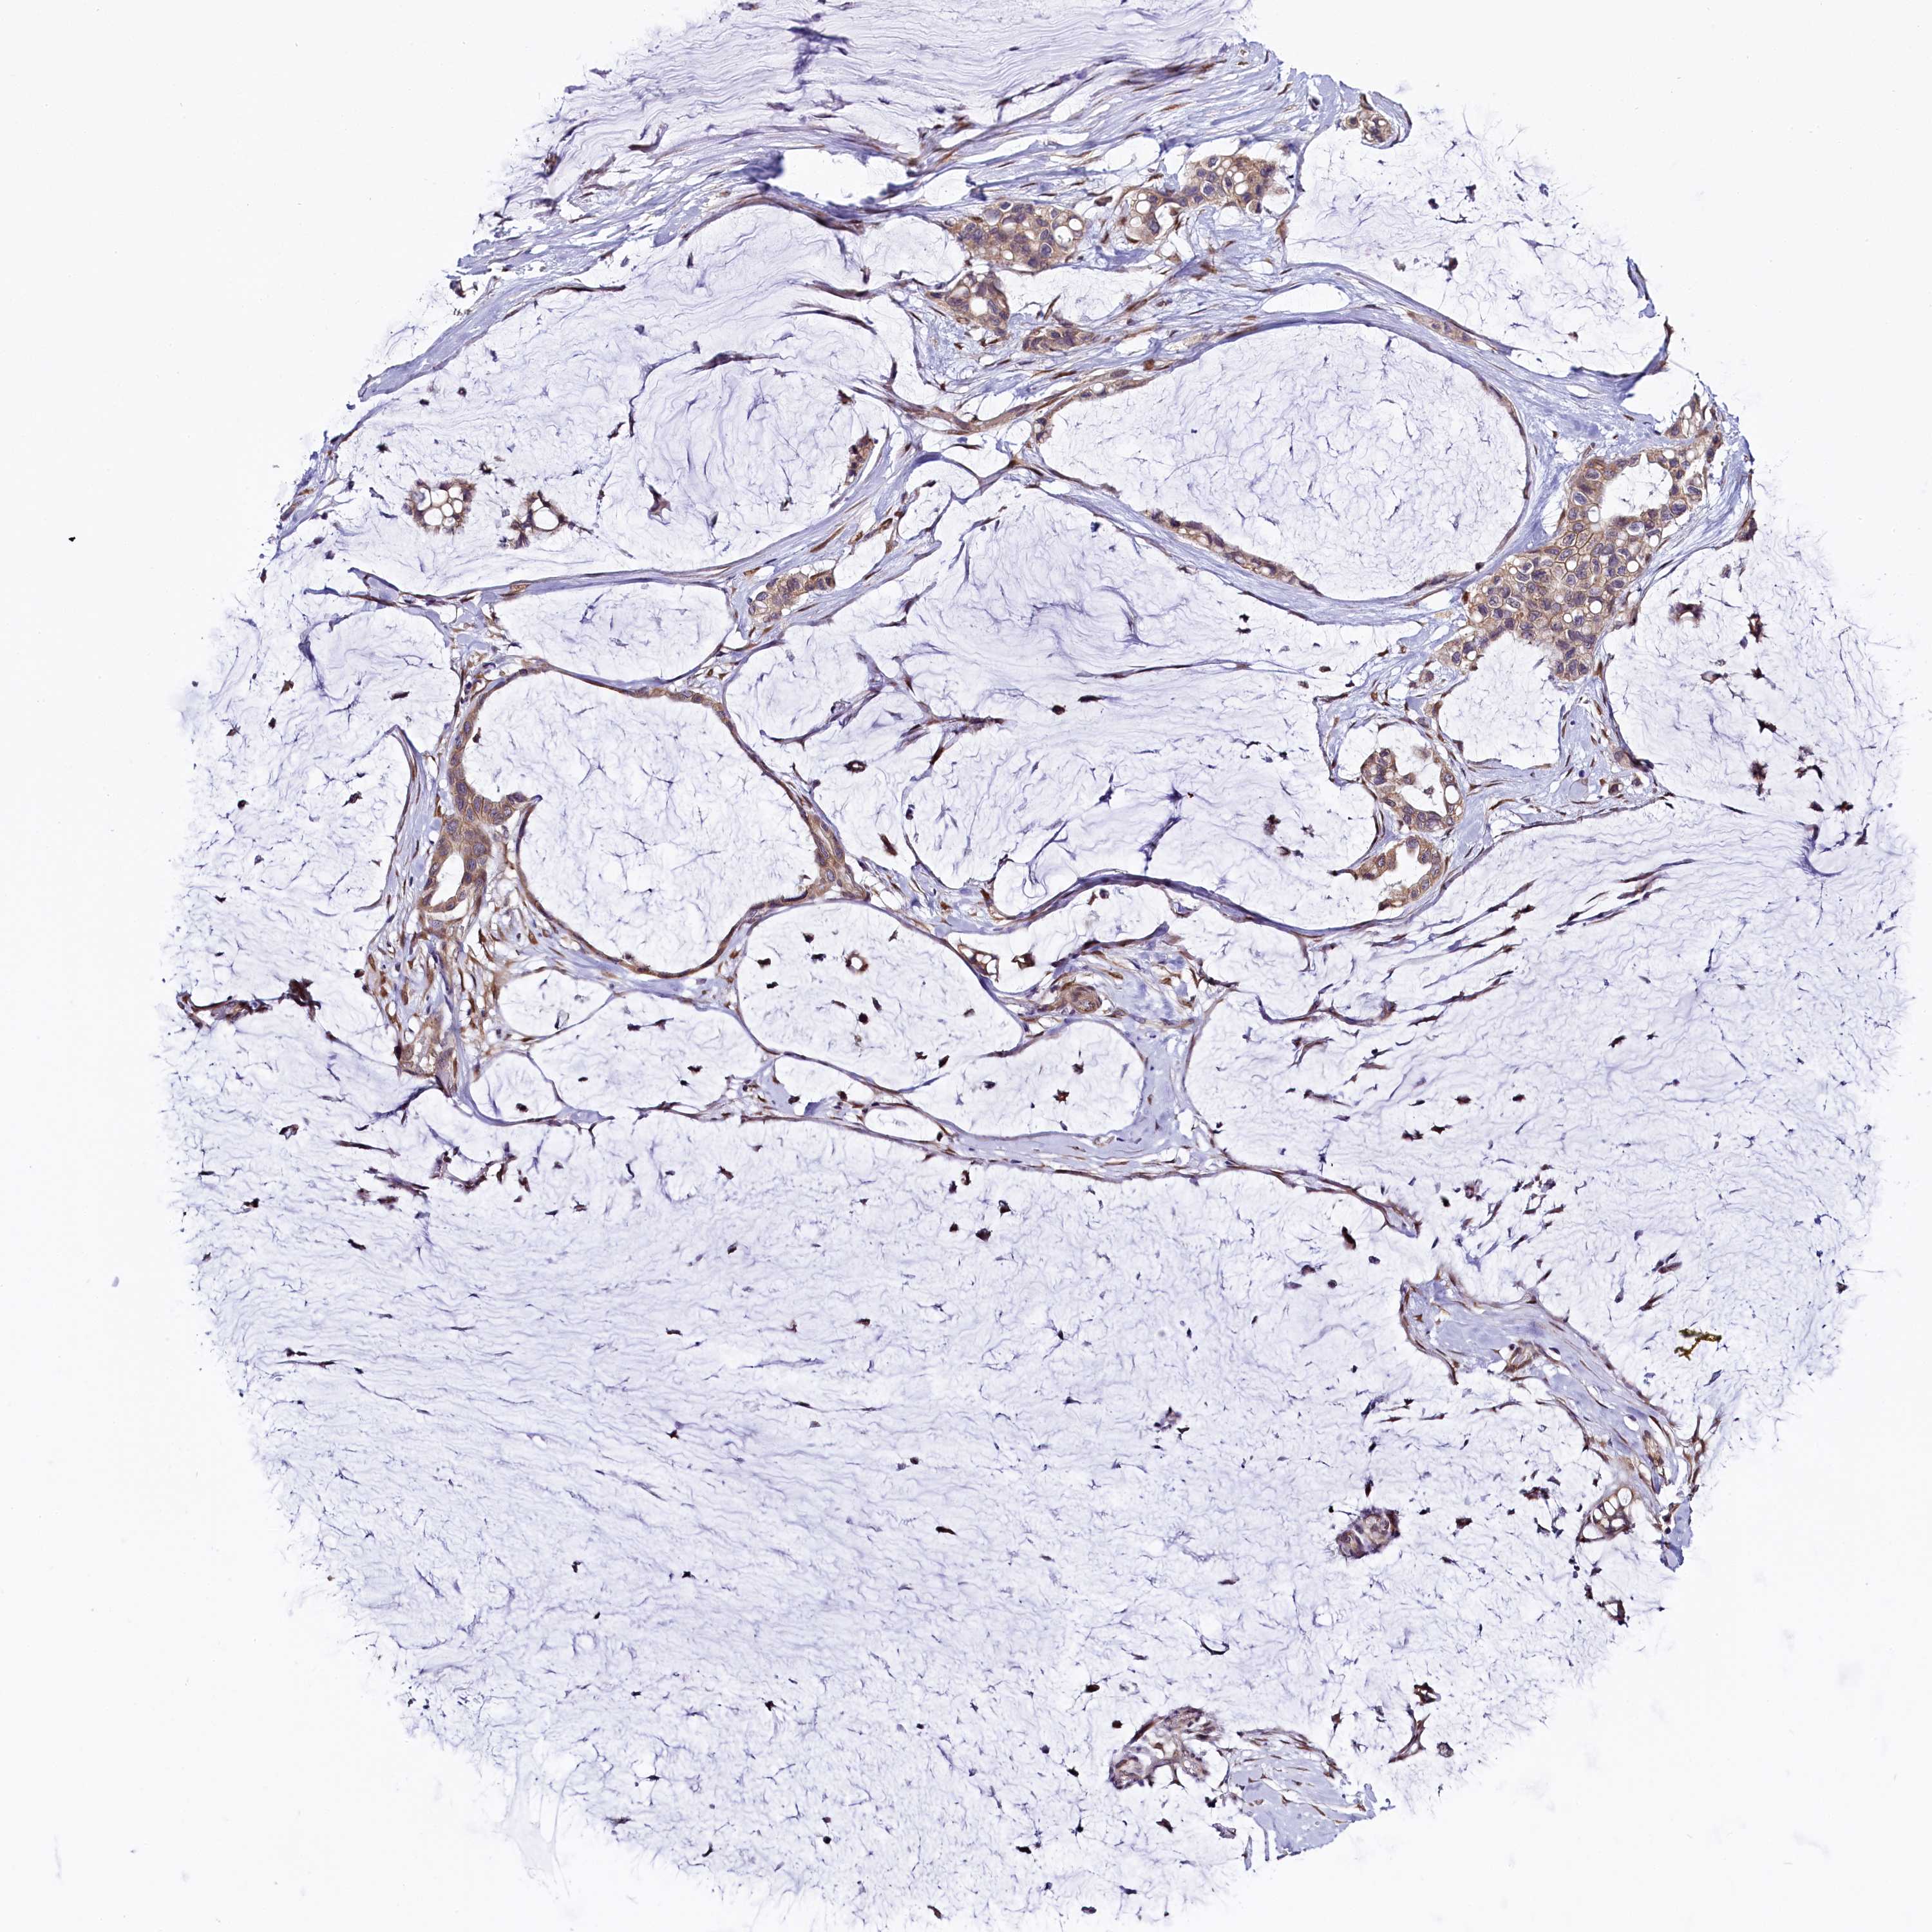

OVARIAN CANCER - Protein expressioni

A mouse-over function shows sample information and annotation data. Click on an image to view it in a full screen mode. Samples can be filtered based on level of antibody staining by selecting one or several of the following categories: high, medium, low and not detected. The assay and annotation is described here.

Note that samples used for immunohistochemistry by the Human Protein Atlas do not correspond to samples in the TCGA dataset.

Antibody stainingi

Antibody staining in the annotated cell types in the current human tissue is reported as not detected, low, medium, or high, based on conventional immunohistochemistry profiling in selected tissues. This score is based on the combination of the staining intensity and fraction of stained cells.

Each image is clickable and will lead to virtual microscopy that enables deeper exploration of all samples and also displays staining intensity scores, fraction scores and subcellular localization as well as patient and tissue information for each sample.

Antibody HPA041412

Antibody HPA056006

Cystadenocarcinoma, serous, NOS

Carcinoma, endometroid

Cystadenocarcinoma, mucinous, NOS

Carcinoma, NOS